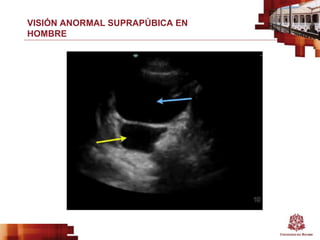

VISIÓN ANORMAL SUPRAPÚBICA EN

HOMBRE